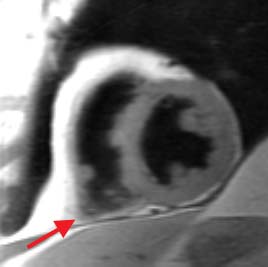

Long axis blood suppressed image obtained at diastole

during suspended respiration. The arrow indicates thinning of the right

ventricular apical wall.